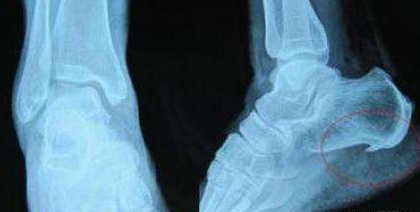

腰椎骨质增生病理变化主要有椎间盘退变、椎体边缘骨质增生及关节突的增生。在成人椎回盘缺乏直接的血液供应,仅靠通过软骨板的淋巴液营养其腰部劳损又大。因此,在20岁以后就进入退变期。退变的椎间盘逐渐失去水分,使椎何隙变狭窄,纤维环松弛向周缘膨出。椎体边缘骨膜被撕裂掀起,骨膜下微微出血机化、纤维化,最后骨化而形成增生的骨质。椎间盘的退变、椎间隙变窄、纤维环的松弛,脊柱的剪力则落到关节突关节上,并使其承受较大的压力。这样,就使小关节面的软骨由于营养差且负重大而逐渐变为黄色,不透明,出现粗糙不平的局限性软化区。渐渐的磨损脱落,软骨下骨质产生硬化及边缘生,以致关节突肥大、松弛.由此可见腰椎骨质增生和慢性劳损、年龄及损伤有密切的关系。举重运动员、搬运工人等使用腰部工作的人腰椎增生的发生率明显增多,且出现的年龄较早。但是在同工种同年龄的人中其增生的发生和程度也有不同。因此,腰椎骨质增生和个人及本身的代谢、内分泌等因素有一定的关系。